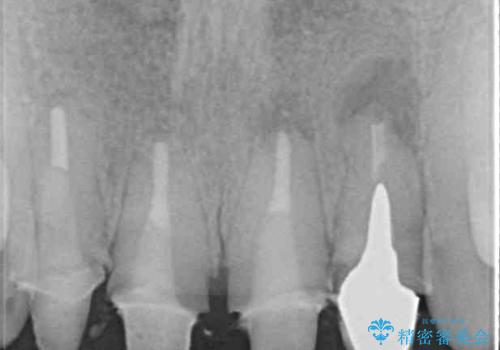

根尖病変が原因で、膿が出てきている歯があったため、仮歯を置き換える際に根管治療を行うこととしました。

仮歯を変えたことで歯肉の腫れは引き、根管治療も功を奏して膿の出口はきれいに消退しました。